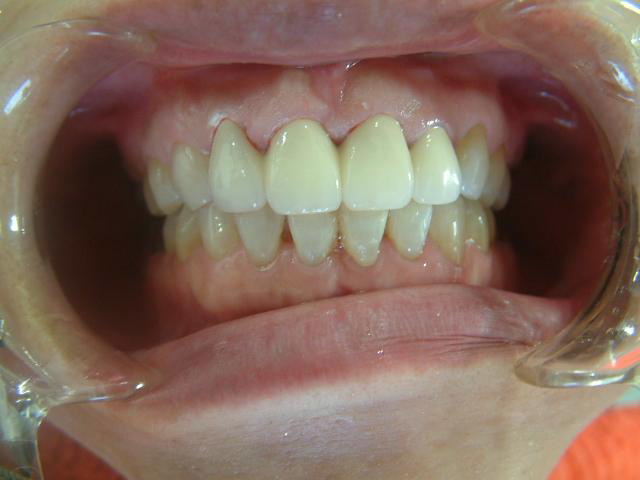

補綴物物 完成

患者さんから「出っ歯にならないよに!」

と再度念を押されたので

出来る限り内側に入れて製作しました。

模型上では、1.1下部孤形空隙が広いように

見えますが、歯肉模型にて調整して

歯肉を圧迫せず、息が漏れることが無いように

調整しました |

初診の状態とセット時の状態